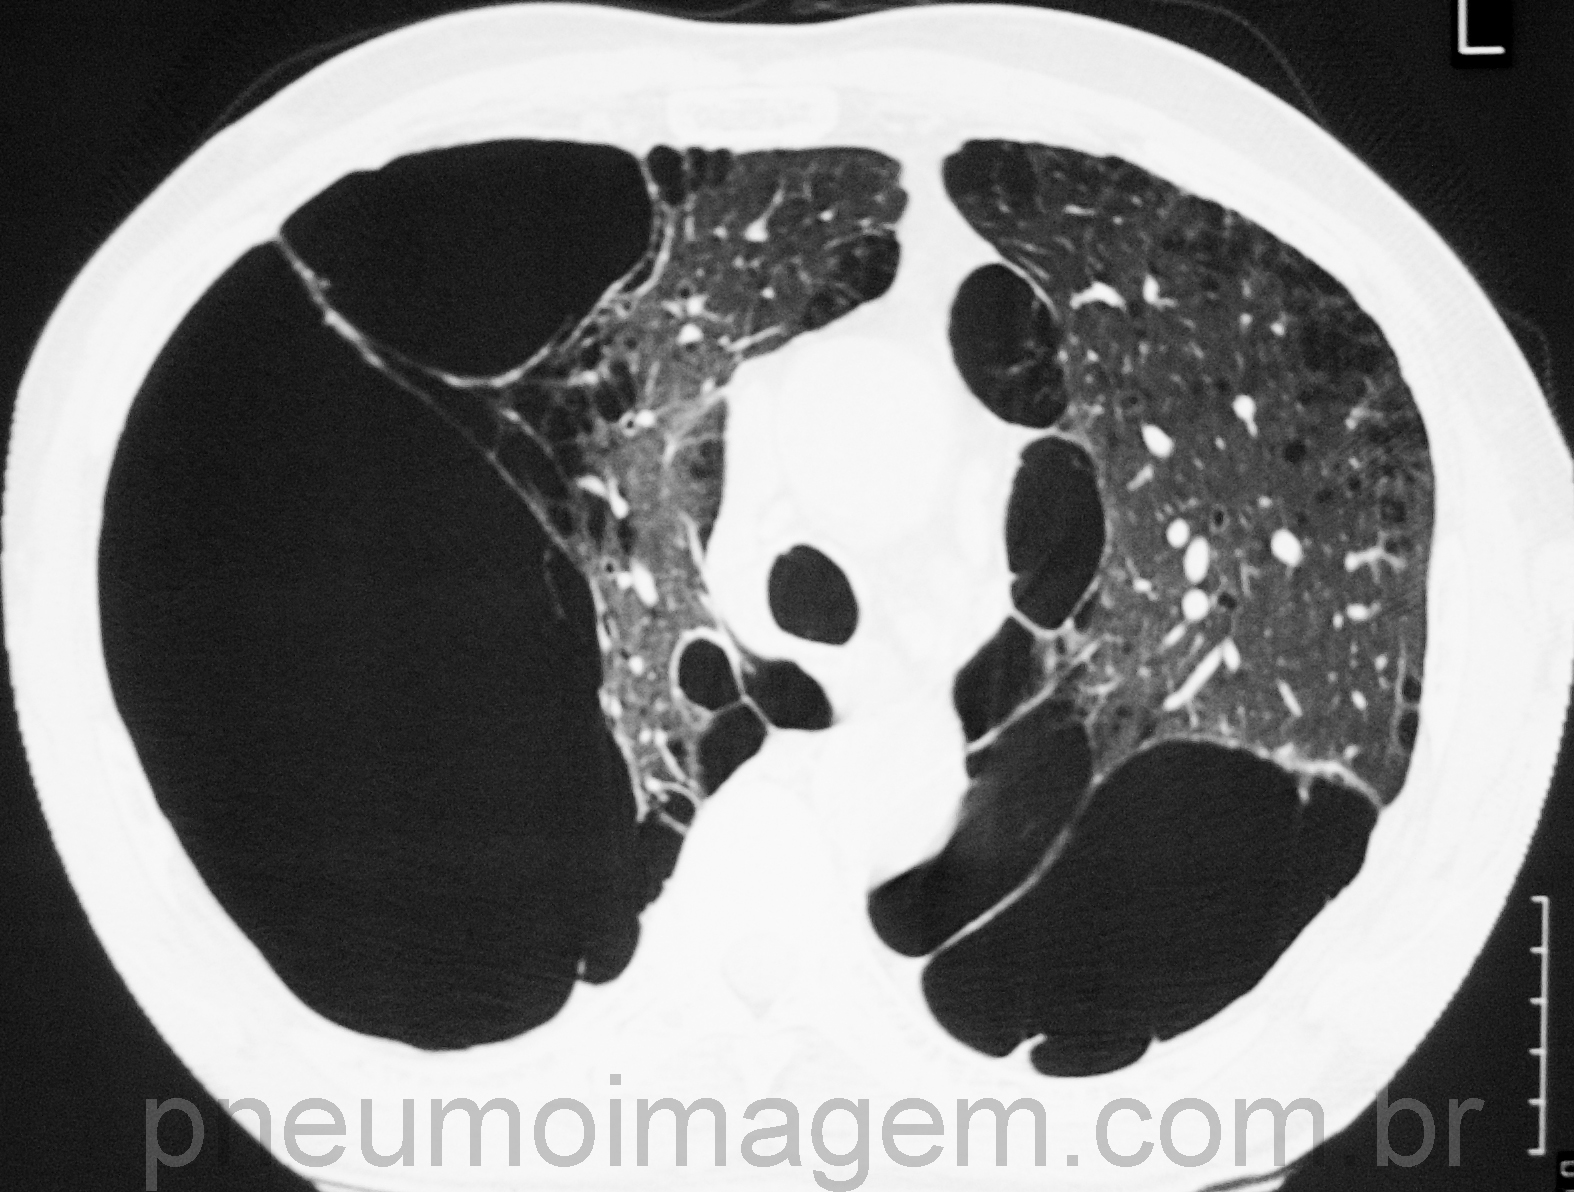

Tomografia de tórax com enfisema pulmonar.

O ar que penetra pelo nariz e pela boca chega ao interior dos pulmões percorrendo a traqueia e os brônquios. Na pessoa que tem DPOC ocorre uma inflamação crônica dos brônquios (bronquite crônica) e uma destruição dos alvéolos, que são as células que formam os pulmões, o que origina o enfisema pulmonar (foto). A DPOC tem evolução progressiva e irreversível.